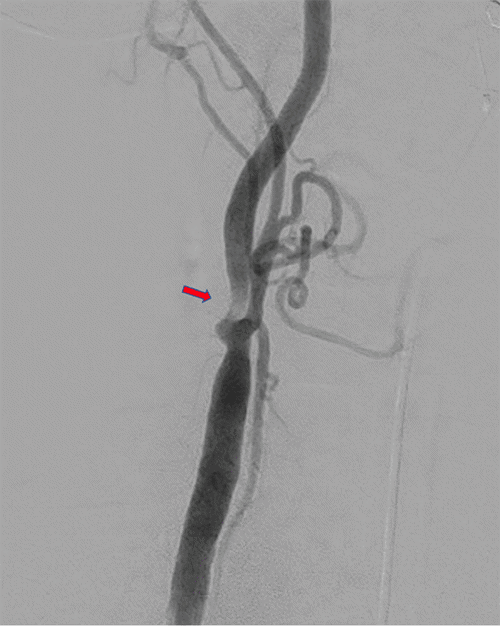

After recovering from his left TCAR and being seen in follow-up, he then underwent an elective right TCAR. Right carotid angiogram demonstrated severe focal ICA stenosis consistent with preoperative imaging (Figure 3A). Angioplasty was performed with a 5 × 20 mm balloon, followed by deployment of a 9 × 30 mm ENROUTE Transcarotid Stent (Silk Road Medical, Sunnyvale, CA). The completion angiogram demonstrated a satisfactory result (Figure 3B). He was hemodynamically stable and discharged home on postoperative day 2 without new neurologic symptoms. The patient was discharged on dual antiplatelet therapy with aspirin 81 mg once daily and clopidogrel bisulfate 75 mg once per day.

Figure 3. Right Carotid Angiogram During TCAR Procedure Before A) and After B) Angioplasty and Stent Deployment. Published with Permission

A.

B.